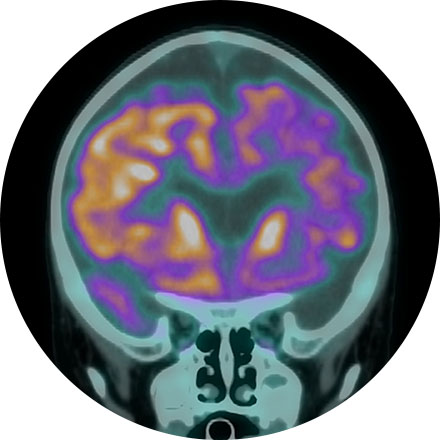

FDG Brain PET/CT

A FDG brain PET/CT is used to image the metabolic function of the brain. Positron emission tomography (PET) uses small amounts of radioactive materials called radiotracers, a special camera, and a computer to help evaluate the brain. It is most commonly used to calculate the degree and pattern of brain volume loss, which allows the neuroradiologist to assess for different types of neurodementia syndromes. It can also help differentiate recurrent brain tumor vs. radiation change after a patient has had brain surgery. Additionally, it can help identify the seizure focus in patients with epilepsy.